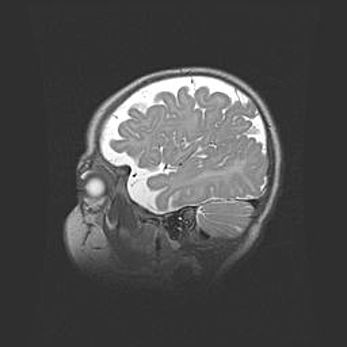

Подострая гематома правой гемисферы мозжечка.

Наружная гидроцефалия.

Возраст: 15 дней

Вес: 3100 г

Пол: женский

Окружность головы: 37 см

Срок гестации: 35-36 недель

При открытой наружной форме гидроцефалии у новорожденных расширяются и переполняются субарахноидные пространства.

Кровоизлияния в мозжечок имеют две клинико-анатомические формы: полушарные гематомы и кровоизлияния в червь.

К появлению этой патологии может привести: повреждения головного мозга, возникающие в результате асфиксии и гипоксии плода при беременности, или травмы во время родов. Редко гематома мозжечка может быть результатом первичной коагулопатии и сосудистой мальформации, диссеминированном внутрисосудистом свертывании, изоиммунной тромбоцитопении.